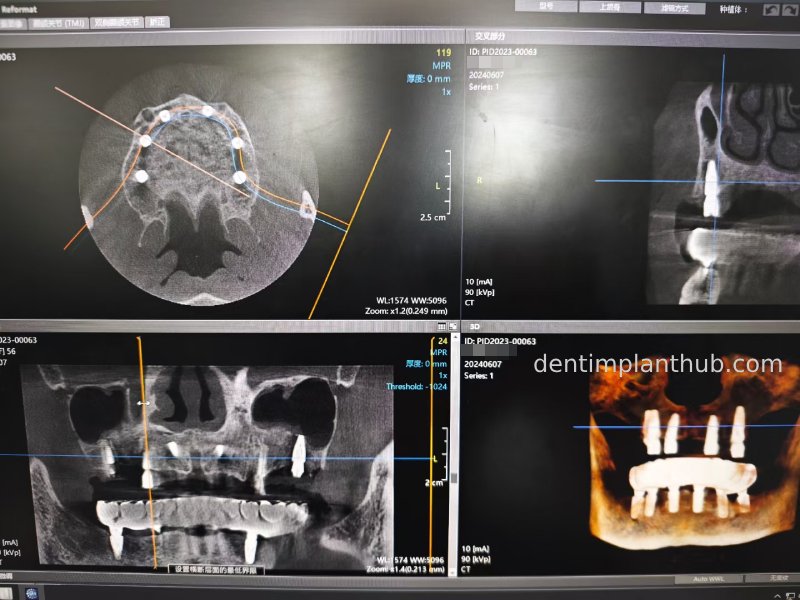

CBCT review results on 13 May '24

46

44

42

32

34

36

Maxillary condition as shown by CBCT on 13/5/24

16

14

12

22

24

26